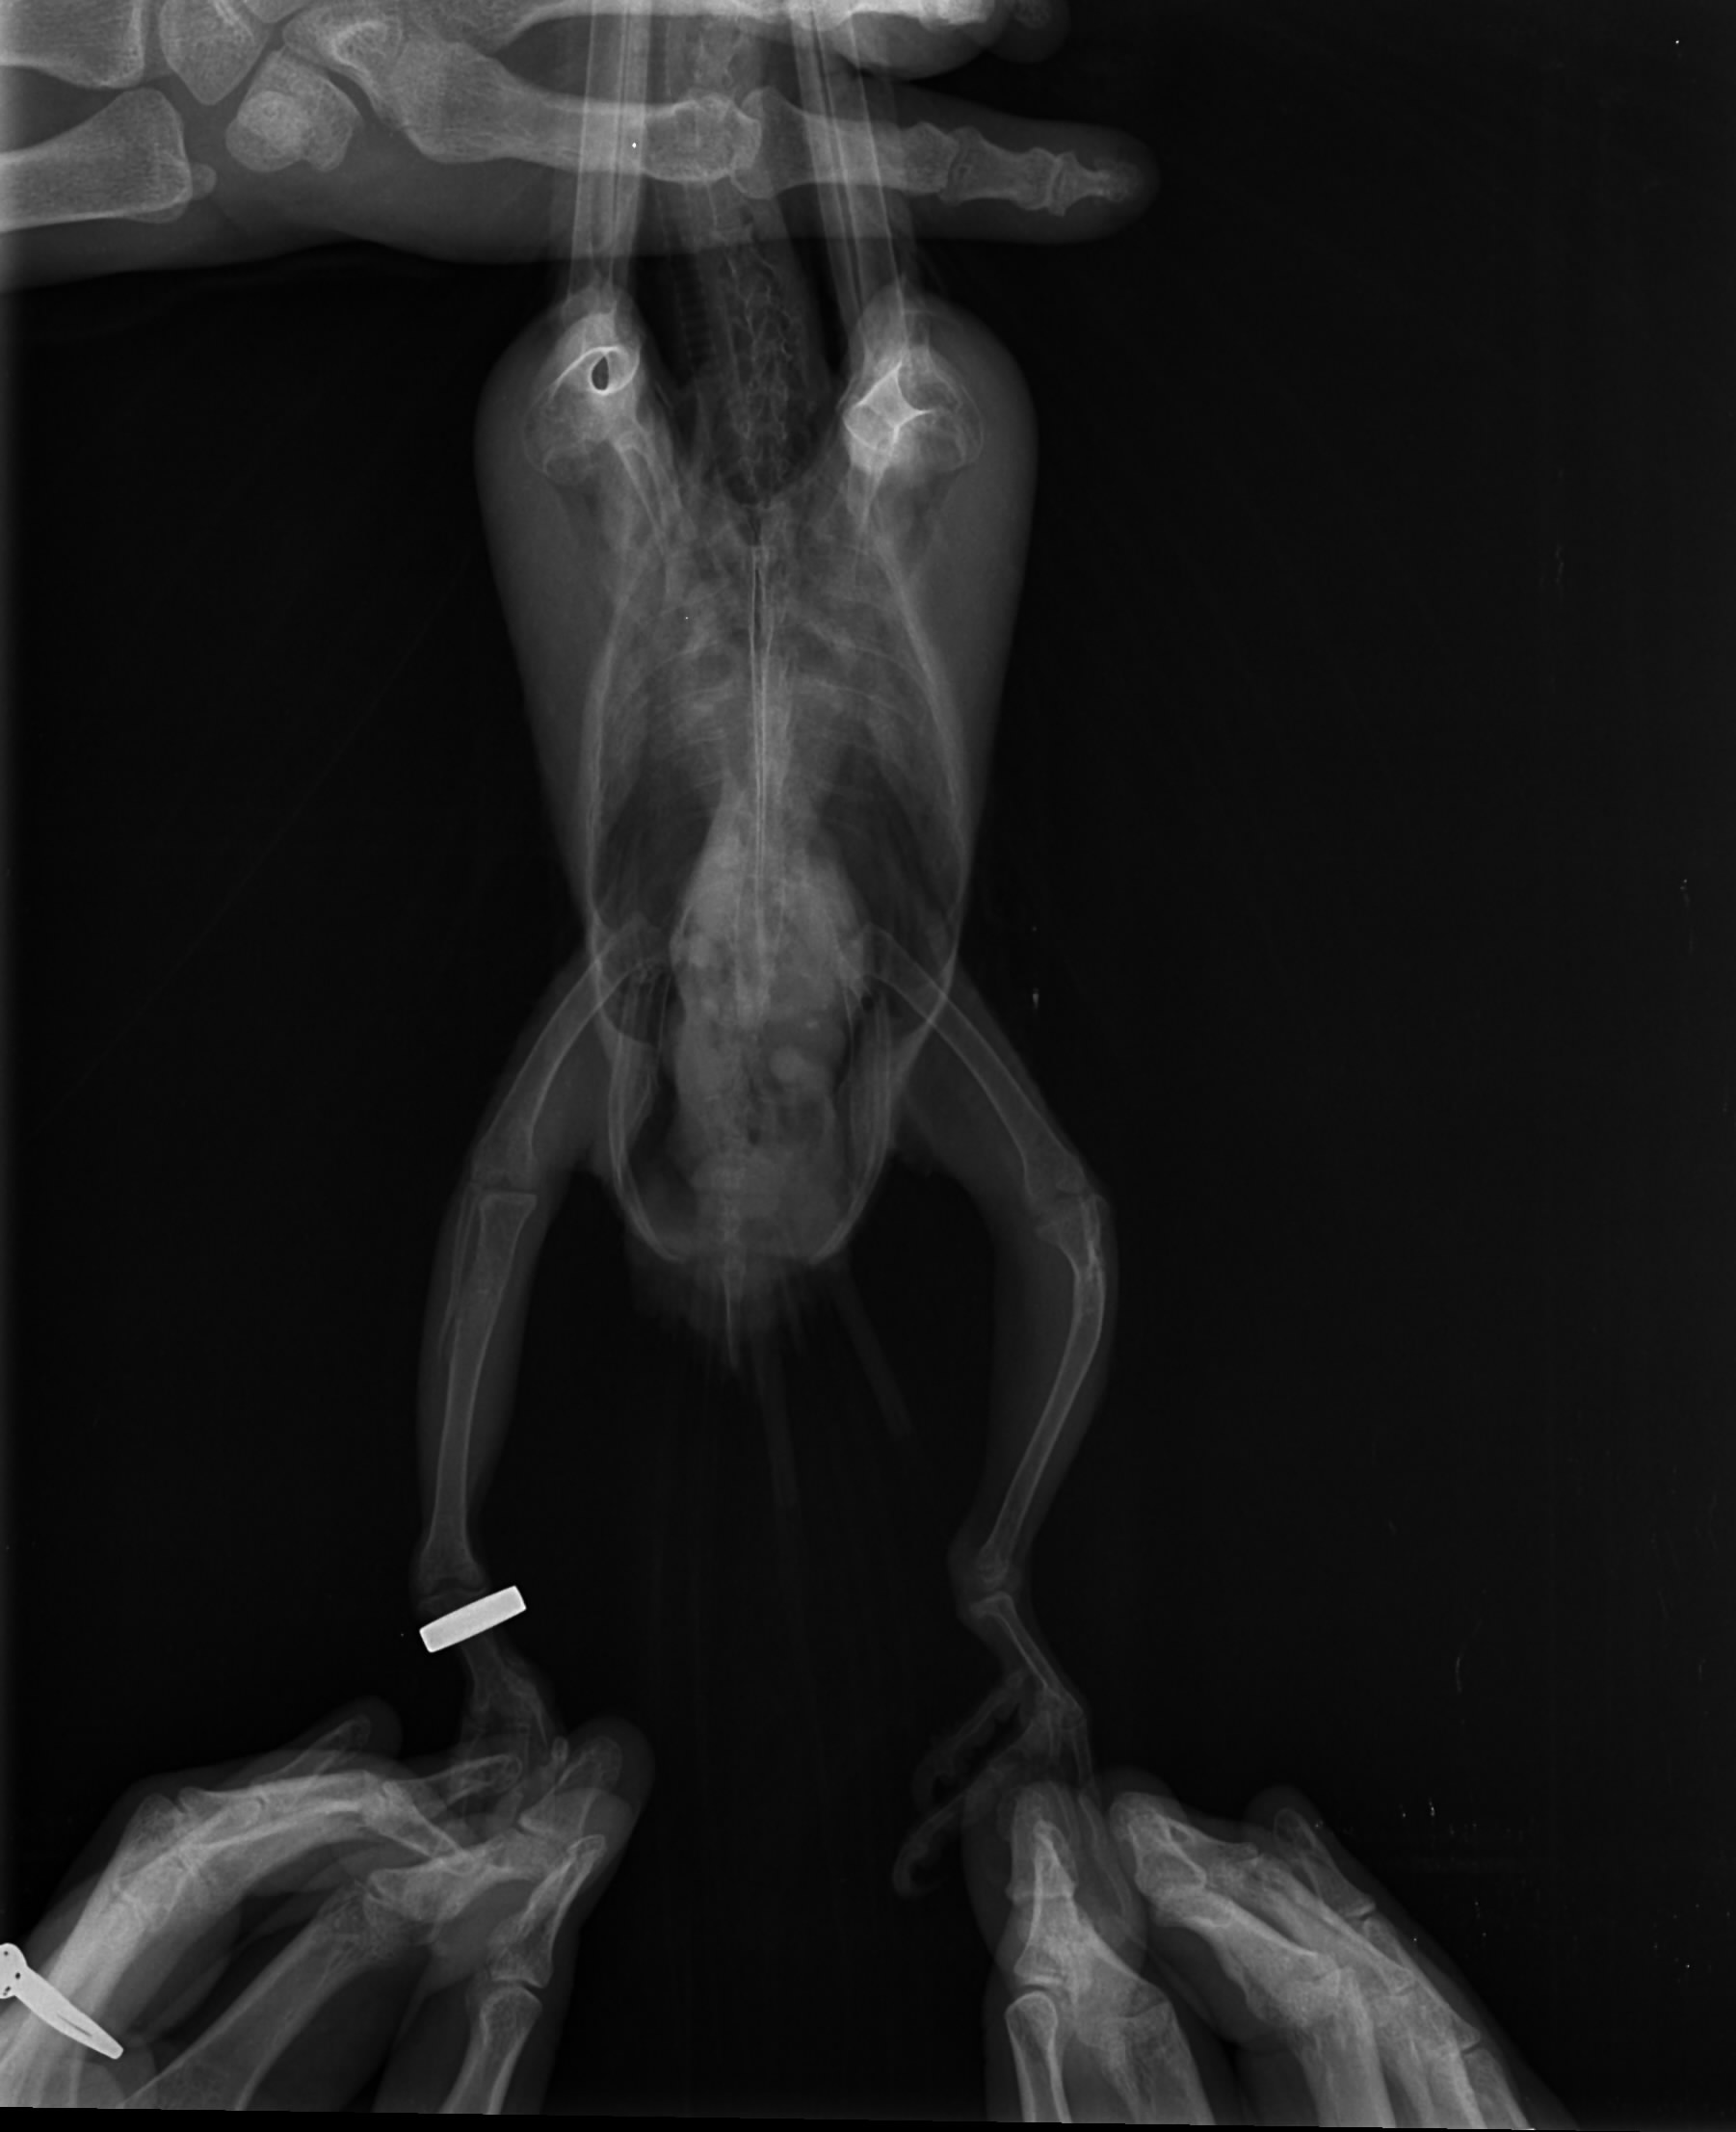

Witam i proszę o pomoc. Może ktoś z Was miał już takie problemy. Mam młodą lorke od hodowcy z forum nie będę teraz rozwodzić się na temat tego od kogo i dlaczego ale młody nie chce latać. Pierwszy raz mam taką sytuację , że młoda półroczna papuga nie chce latać. Od samego początku podkurczał łapki w piąstkę ale składałam to na karb masy ciała bo był dużym pisklakiem. Niestety nie wyłapałam tego wcześniej i za to się obwiniam :( Ma okropnie krzywe kości. Dojechał do mnie jak miał prawie 3 miesiące więc ten intensywny wzrost już był zakończony. Ptak wówczas już nie przyrasta na masie a wręcz ją gubi na usamodzielnieniu. Dokarmiałam go jeszcze miesiąc dokładając wapń do papki dwa razy w tygodniu ze względu na silne przebarwienia na skrzydłach (zółte lusterka) Ale nie wyłapałam tak silnej krzywicy w układzie kostnym. Na zdjęciu rtg załączonym widać w jakim stanie są kości. W dodatku nie jest to odosobniony przypadek w tej hodowli bo jedna z wcześniejszych papug połamała nogę i też weterynarz stwierdził jako przyczynę dużą krzywicę. Zwróćcie też uwagę na zdjęcie samiczki może jestem przewrażliwiona ale wydaje mi się że to również spora krzywica. Wady występują u piskląt od różnych par więc wydaje mi się , że problemem jest tutaj ewidentnie żywienie. Wcześniej do głowy mi nie przyszło bo hodowla polecana przez lata przeze mnie ale teraz nie wiem co o tym myśleć:( Może ktoś z Was miał już takie problem ja przyznam że przez 20 lat mi się takie nie przytrafiły. Czekam dzisiaj na wyniki biochemi. Suplemenuje teraz młodemu D3 i wapń zobaczymy co jeszcze wyjdzie w biochemii :( Ale nóg się już wyprostować nie da :( Problem zdaje się dotyczy również skrzydeł niestety na rtg nie ma wszystkich kości :( Czekam na wizytę u dr. Piaseckiego na początku marca po jego powrocie z Australii :( a do tego czasu futruje małego witaminami i minerałami mając nadzieję że zniesie te wysokie dawki witaminy D3 zgodnie z zaleceniem lekarzy bez szwanku na zdrowiu:( No i wyrzucam sobie cały czas że nie skoarzyłam i nie dojrzałam tego wcześniej :(

Na zdjęciu strony nie są oznaczone. Po prawej stronie zdjęcia (jak patrzę na monitor ) pod stawem kolanowym, też są jakieś zwapnienia. Na ptakach się nie znam, ale u ludzi, tak właśnie wygląda kość po wyleczonym złamaniu (narasta więcej okostnej).

Zdjęcie boczne słabe - za ciemne - ale może na negatoskopie lepiej widać.

Dzięki za informacje. Witaminę D3 podaję właśnie z wapniem i na odwrót. Złamanie jest widoczne na cienkiej kości, ale kości mają wyraźne zgrubienia i zwapnienia. Źle to wygląda niestety ale po kilku dniach suplementacji ptak zaczyna stawać na jednej łapce a drugą próbuje chwytać pokarm i zabawki. Znacznie się też ożywił, chociaż do miesiac starszej samiczki z mojego chowu mu bardzo daleko :( Nie widać starych złamań na kości ale te zgrubienia są potencjalnym miejscem w którym kość może w każdej chwili chrupnąć i to mi właśnie spędza sen z powiek :( Lewa noga jest bez obrączki i to ona jest wyraźnie w gorszym stanie niż prawa której niestety też wiele brakuje do normalności